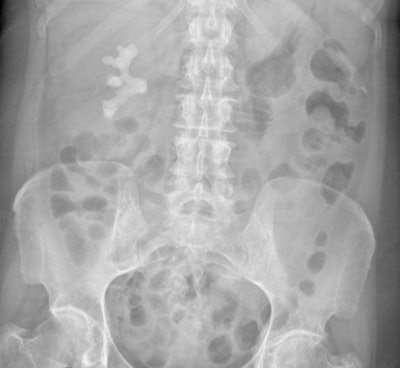

Digital abdominal x-ray shows large staghorn renal calculus, which is the white density below the ribs. But are such investigations of any great value when CT and ultrasound are more sensitive?To evaluate the efficacy of AXR in the assessment of acute abdominal pain, and to provide evidence for a change of imaging practice, Yamamoto and colleagues conducted a retrospective analysis of abdominal x-rays performed for acute admissions to the emergency department and any subsequent imaging with CT or ultrasound. They included only patients who complained of abdominal pain, were aged older than 16, and were referred initially for AXR.